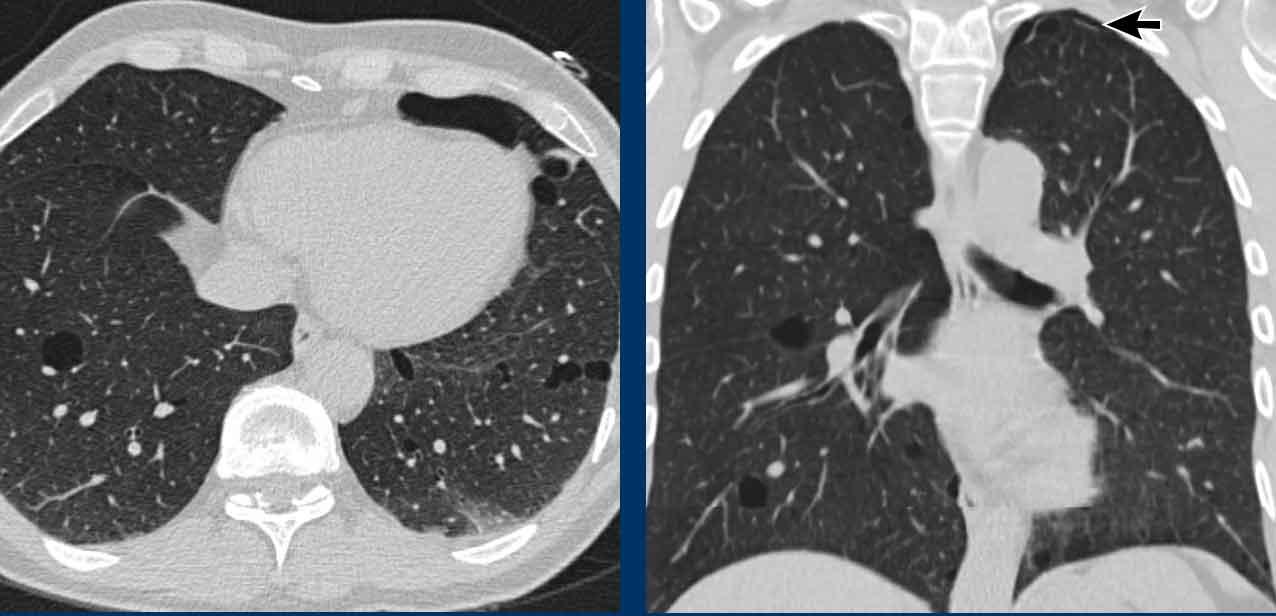

LAM biểu hiện với số lượng lớn các nang hình tròn, bờ đều đặn, phân bố rải rác khắp nhu mô phổi.

Hình ảnh

- Nhiều nang ở một phụ nữ trẻ. Lưu ý hình dạng tròn đều và phân bố lan tỏa.

- Trường hợp LAM nặng. Khi có tiền sử hút thuốc lá, chẩn đoán phân biệt cần đặt ra là LCH (giai đoạn tiến triển).

- Tràn dịch màng phổi (dịch dưỡng chấp) ở bệnh nhân LAM.

- Phân bố lan tỏa trong LAM.

Các hình ảnh này thuộc về một phụ nữ 39 tuổi với triệu chứng khó thở.

Chẩn đoán có khả năng nhất là gì?

Nhận xét hình ảnh

Có nhiều nang thành mỏng.

Lưu ý các nang phân bố đều khắp hai phổi.

Các ngách màng phổi cũng bị tổn thương (mũi tên).

Điều này cho phép loại trừ chẩn đoán LCH.

Chẩn đoán có khả năng nhất là LAM.

Đây là một ví dụ khác của LAM.

Có nhiều nang thành mỏng phân bố đều khắp hai phổi, điển hình cho LAM, nhưng trong trường hợp này kết hợp với tràn dịch màng phổi bên phải (mũi tên).

Các tế bào LAM có thể gây tắc nghẽn hệ thống bạch huyết trong lồng ngực và tạo ra tràn dịch màng phổi dưỡng chấp.

LAM là bệnh phổi dạng nang duy nhất có thể thấy sự kết hợp giữa các nang và tràn dịch màng phổi.

Ngoài ra, nhiều u cơ mỡ mạch máu (angiomyolipoma) được phát hiện ở vùng bụng trên.

Bệnh nhân này được xác định mắc LAM liên quan đến phức hợp xơ cứng củ (TSC – tuberous sclerosis complex).

Tỷ lệ hiện mắc u cơ mỡ mạch máu trong LAM tản phát là 40-50% và trong LAM liên quan TSC vào khoảng 80%.

Đây là trường hợp LAM nặng với nhu mô phổi bị tổn thương lan tỏa.